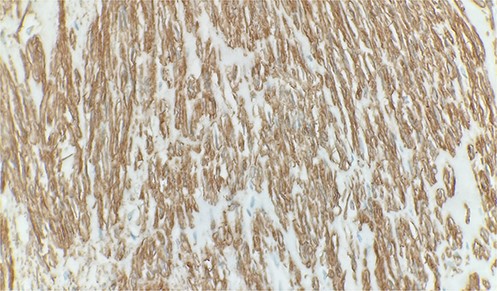

A 70-year-old male patient with a history of prostatic adenocarcinoma presented with testicular swelling. Testicular ultrasound revealed a 4 cm hypoechoic mass at the level of the epididymis. The patient underwent a radical orchiectomy. Pathology demonstrated a 4 cm mass located around the epididymis that was composed of elongated spindle cells arranged in intersecting fascicles. The tumor cells were found to have cigar-shaped nuclei and fibrillary eosinophilic cytoplasm (Fig. 1). Most of the lesions indicated relatively monomorphic cytology. Scattered moderate-to-focally marked nuclear pleomorphism was present. Focal necrosis was present, which may be suggestive of more aggressive biologic behavior. Ki 67% was approximately 10% and the mitotic activity was 7 mitotic figures per 10 high power-fields. The tumor margins were negative, with no invasion of the testicular parenchyma or spermatic cord. Immunohistochemistry showed strong reactivity with desmin and smooth muscle actin (Fig. 2). Overall, findings were diagnostic of low-grade leiomyosarcoma.

Immunohistochemical stain reveals tumor cells are positive for smooth muscle actin. Immunohistochemistry 40×.